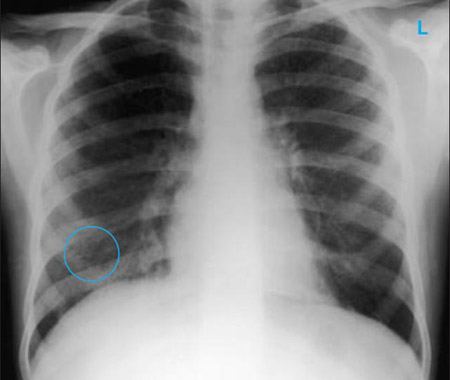

Chest x-ray

A chest x-ray should be obtained early in the evaluation of chronic cough.[38] Although it is not diagnostic of the most common causes, findings may quickly divert the evaluation to causes of greater gravity, such as structural lung diseases. These include lung cancer, pulmonary fibrosis, tuberculosis, bronchiectasis, pneumonia, aspiration, and sarcoidosis.[Figure caption and citation for the preceding image starts]: Chest x-ray showing hyperinflation in a patient with COPD. The hyperinflation is caused by the emphysema component of COPD, rather than the chronic bronchitis that underlies symptoms of coughFrom the personal collection of Dr M. A. Sharifabadand, SUNY at Stony Brook School of Medicine, Department of Pulmonary and Critical Care Medicine, Mineola, New York and Dr J. P. Parsons, The Ohio State University Medical Center, Columbus; used with permission [Citation ends].com.bmj.content.model.assessment.Caption@65a65855[Figure caption and citation for the preceding image starts]: Chest x-ray showing multiple miliary lung metastases (arrows). The primary tumour was a thyroid carcinomaE. Dick, Student BMJ. 2001;9:10-12 [Citation ends].com.bmj.content.model.assessment.Caption@25657fee[Figure caption and citation for the preceding image starts]: Chest x-ray showing left hilar carcinoma (arrow)From: E. Dick, Student BMJ. 2000;8:358-360 [Citation ends].com.bmj.content.model.assessment.Caption@567b9fef[Figure caption and citation for the preceding image starts]: Chest x-ray showing a cavitating right hilar carcinoma (arrow)E. Dick, Student BMJ. 2001;9:10-12 [Citation ends].com.bmj.content.model.assessment.Caption@3d6fa55[Figure caption and citation for the preceding image starts]: Chest x-ray in a patient with bronchogenic carcinoma showing a left-sided pleural effusionFrom: R. Thakkar, Student BMJ. 2001;9:458 [Citation ends].com.bmj.content.model.assessment.Caption@5b46acec[Figure caption and citation for the preceding image starts]: Chest x-ray showing interstitial fibrosis in a patient with amiodarone pulmonary toxicityFrom the personal collection of Dr A. Pataka and Professor P. Argyropoulou, Aristotle University, Thessaloniki, Greece; used with permission [Citation ends].com.bmj.content.model.assessment.Caption@2c3c94b0[Figure caption and citation for the preceding image starts]: Chest x-ray showing pulmonary tuberculosis with cavitationFrom the personal collection of Dr M. Narita, Department of Pulmonary and Critical Care Medicine, University of Washington [Citation ends].com.bmj.content.model.assessment.Caption@3dd7f84b[Figure caption and citation for the preceding image starts]: Chest x-ray showing multiple discrete nodules throughout both lungs (one of which is circled) in a patient with miliary tuberculosisE. Dick, Student BMJ. 2001;9:10-12 [Citation ends].com.bmj.content.model.assessment.Caption@23fa6365[Figure caption and citation for the preceding image starts]: Chest x-ray with lack of normal tapering producing a tram line in a patient with bronchiectasisFrom the personal collection of Dr S.M. Bhorade, University of Chicago Medical Center; used with permission [Citation ends].com.bmj.content.model.assessment.Caption@36b415f2[Figure caption and citation for the preceding image starts]: Chest x-ray with dilated and thickened airways in a patient with bronchiectasisFrom the personal collection of Dr S.M. Bhorade, University of Chicago Medical Center; used with permission [Citation ends].com.bmj.content.model.assessment.Caption@78e208fa[Figure caption and citation for the preceding image starts]: Chest x-ray showing increased opacification of the right perihilar region and superior segment of the right lower and upper lobes consistent with worsening aspiration pneumoniaFrom the personal collection of Dr R. Kanner, University of Utah School of Medicine [Citation ends].com.bmj.content.model.assessment.Caption@71be2c1f[Figure caption and citation for the preceding image starts]: Portable chest x-ray with bibasilar opacities, worse on the right than the left, in a patient with hospital-acquired pneumoniaFrom the personal collection of Dr F. W. Arnold, Division of Infectious Diseases, Department of Medicine, University of Louisville School of Medicine [Citation ends].com.bmj.content.model.assessment.Caption@2c704497[Figure caption and citation for the preceding image starts]: Chest x-ray showing early ill-defined opacities of the right upper lobe above the minor fissure consistent with early changes of aspiration pneumoniaFrom the personal collection of Dr R. Kanner, University of Utah School of Medicine [Citation ends].com.bmj.content.model.assessment.Caption@23fa54d0[Figure caption and citation for the preceding image starts]: A. Portable upright chest x-ray before aspiration; B. Chest x-ray 1 hour after aspiration, showing bilateral diffuse alveolar infiltrates, worse at the bases on the right sideFrom the personal collection of Dr S. Murgu and Dr H. Colt, University of California at Irvine Medical Center [Citation ends].com.bmj.content.model.assessment.Caption@7860be3a[Figure caption and citation for the preceding image starts]: Chest x-ray showing bilateral hilar adenopathy in a patient with sarcoidosisFrom the personal collection of Dr M.P. Muthiah, Division of Pulmonary and Critical Care and Sleep Medicine, University of Tennessee [Citation ends].com.bmj.content.model.assessment.Caption@31e94b4e